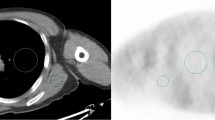

We assumed that the torso cross-sections of all of the patients were oval and easily measured. We retrospectively measured the cross-sectional areas and the OCSs of the liver in the CT images from 61 patients (group 1). The cross-section was measured by extraction of an outline of the torso on a transaxial image by use of Xeleris software. The OCSs were calculated from the major and minor axes (Fig. 1) from Eq. 2, as follows:

where π is the circular constant (3.14). We determined the relationships between the torso cross-sections and the OCSs in all of the patients by using the liver sections among the transverse CT images, and we then determined the correlation between the measured cross-section and the OCS for each patient.

Figure 7 shows the axial and coronal PET images that were acquired from three patients for 120 s, and it shows a comparison of these images with those obtained after adjustment of the acquisition times. The uniformity of the liver images from an overweight patient (bottom column) improved when Eq. 5 was applied. The quality of the optimized PET images improved in normal-weight and overweight patients, but it remained the same in underweight patients.

Comparison of the transaxial and coronal positron emission tomography images attained at conventional (120 s) and optimal acquisition times. The standardized uptake value in each image is scaled from 5.0 to 0.0. Image quality after 120 s of acquisition (left) is comparable to that after optimization (right) for the lighter patient (top column) and had clearly improved for normal-weight (middle column) and overweight (bottom column) patients. BMI body mass index, NEC noise-equivalent count, OCS oval cross-section